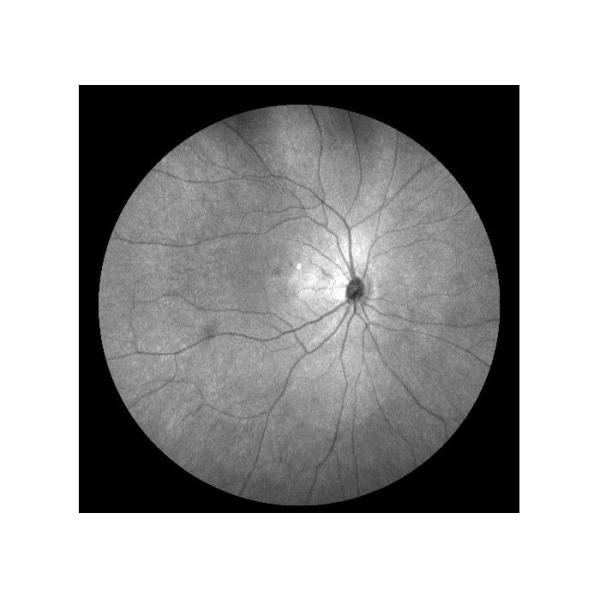

| 4 |  | Auto Fluorescence(AF) | To record fundus fluorescent material distribution in normal or pathology condition |

Cases

Retina Angiograph Digital 160° Ophthalmic Equipment Images |